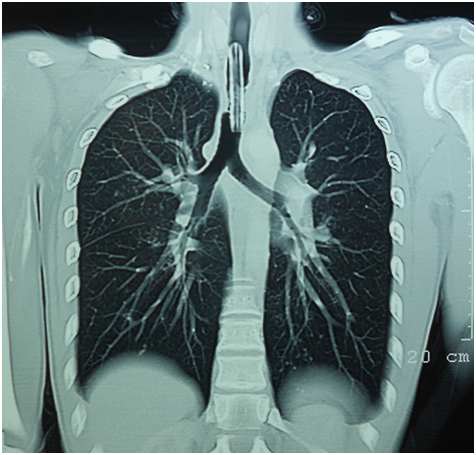

The patient was thoroughly evaluated with computed tomography scan of chest (Figure 1) and video bronchoscopy (Figure 2) and found to have severe tracheal stenosis and therefore, was planned for Tracheal Resection with end-to-end anastomosis under cross-field general anesthesia. The patient was placed supine with extended neck. The procedure was started with a transverse neck incision involving tracheostomy wound. The tracheostomy tube was removed and replaced with a sterile Flexometallic endotracheal (ET) tube with ventilatory circuit by one of the assistant through which general anesthesia was continued. Peristomal dissection was carried out and trachea freed from the skin. Cervical part of the trachea was mobilized. To reach the stenosed segment of trachea, upper median sternotomy was done. The diseased stricture segment was approximately 2cms in length and about 1.5cms from the stoma. The intervening area between the tracheostomy stoma and strictured segment was unhealthy with thinned out tracheal wall. Decision was taken to resect the trachea from proximal to stoma to distal to stenosis including the intervening unhealthy segment which amounted to nearly 4.5cms of tracheal length. In order to achieve adequate length for anastomosis, laryngeal drop was performed by extending the neck and raising the flaps. Trachea was mobilized completely and the diseased segment as described was resected. Airway was established by passing the flexometallic ET tube into the distal tracheal segment. However, adequate length for tension free anastomosis was still not achieved.

Figure 2 Videobronchoscopy revealed tracheal narrowing by granulation tissue.

PTTS is an iatrogenic lesion caused by cicatricial healing of an area of transmural injury to the airway. Tracheostomy most commonly for ventilatory support can result in local ischemia or necrosis and subsequent stenosis during the phase of healing by secondary intention. Necrosis induced by pressure related loss of regional blood flow is the central injury leading to PTTS.3 The blood supply of the trachea is segmental. Blood vessels perforate the tracheal wall at each interannular space and arborise within the submucosa. The tracheal rings receive their blood supply solely from this submucosal plexus.4,5 Compression of submucosa by the cuff of an ET tube or tracheostomy tube (especially when the cuff pressure exceeds the mucosal capillary pressure i.e. 30mmHg of the trachea) can thus cause regional ischemia of the cartilaginous rings leading to ulceration and chondritis of the tracheal cartilage followed by fibrotic healing and progressive tracheal stenosis typically within 3-6weeks.3,6 Various factors (Table 1) can facilitate these circumstances.3 This etiopathogenesis explained our case also as well defined granulation tissue caused tracheal narrowing (Figure 2). The lesion is usually within 3-4cms of the cricoids cartilage i.e. the site of tracheostomy. In our case also thee lesion was 2cms below the tracheostomy opening extending for 2.5cms and ending 4cms above the carina.